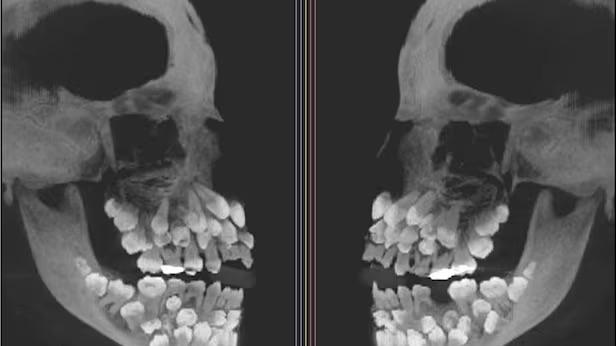

劉泳銦表示,兒童常見的口腔和牙齒問題包括蛀牙、門牙創傷、乳齒過早脫落、磨牙、牙齒染色、用口呼吸(多因上呼吸道阻塞)導致下顎發育不良等問題。此外,使用奶嘴、吸吮拇指、長時間使用奶瓶等會導致牙齒不齊及咬合問題,舌繫帶過短亦會引致進食、牙齒、下顎發育及呼吸道問題。

上呼吸道阻塞和舌繫帶過短,如何影響孩子的牙齒和下巴發育?這是一般家長較少留意的,劉泳銦指,「研究表明,上呼吸道阻塞可能會對兒童的牙齒和下顎發育造成不良影響,例如導致下顎骨錯位、牙齒彎曲和更多齲齒(蛀牙)。除此之外,上呼吸道阻塞也可能使兒童出現顱顏異常的風險增加,例如下顎狹窄、開咬、下顎變小。而舌繫帶過短會導致牙齒錯位、下顎和呼吸道發育不良,使嘴巴和呼吸道變小,影響咀嚼、呼吸或導致睡眠窒息症。」